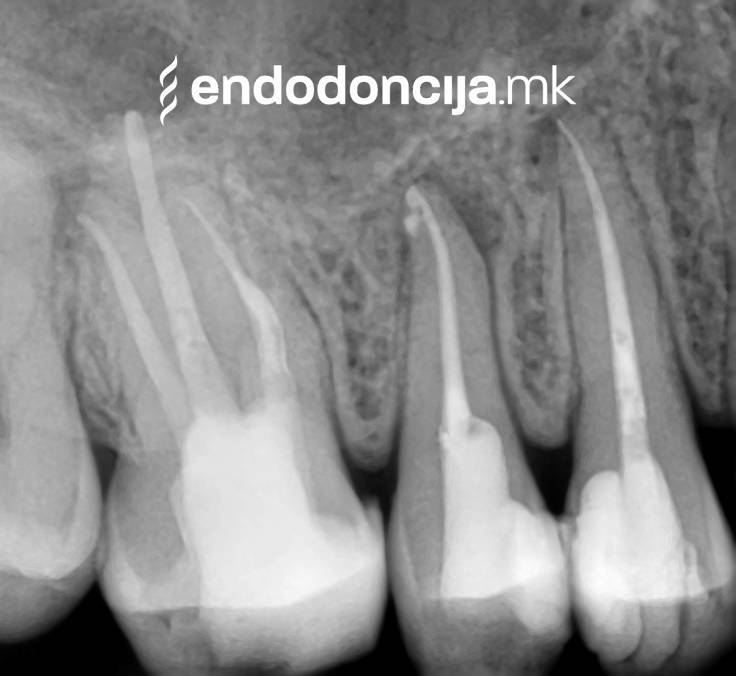

Στο Ειδικό Τμήμα Ενδοδοντικής, αντιμετωπίζουμε τους ασθενείς μας στο υψηλότερο επαγγελματικό και διαγνωστικό επίπεδο. Οι μονάδες θεραπείας μας είναι εξοπλισμένες με τα πιο σύγχρονα χειρουργικά μικροσκόπια, τα οποία υποστηρίζουν μια λεπτομερή αναπαράσταση και προετοιμασία ρίζας και προσφέρουν ένα εντελώς νέο επίπεδο ακρίβειας. Ο νεότερος ενδοδοντικός εξοπλισμός, όργανα και υλικά πλήρωσης χρησιμοποιούνται. Με αυτόν τον τρόπο μπορούμε να διατηρήσουμε τη θεραπεία όσο το δυνατόν συντομότερη, ακόμη και σε περίπλοκες περιπτώσεις, και να αποφύγουμε την απώλεια δοντιών.

Οι υπηρεσίες του Ειδικού Τμήματος Ενδοδοντικής δεν περιορίζονται καθόλου στη συμβατική επεξεργασία ριζικών καναλιών. Αντιμετωπίζουμε αποκλειστικά τους ασθενείς μας με τα νεότερα υλικά και όργανα με μικροσκόπιο, προκειμένου να είμαστε σε θέση να καθαρίσουμε εντελώς και να προετοιμάσουμε όλα τα κανάλια πριν τα γεμίσουμε.